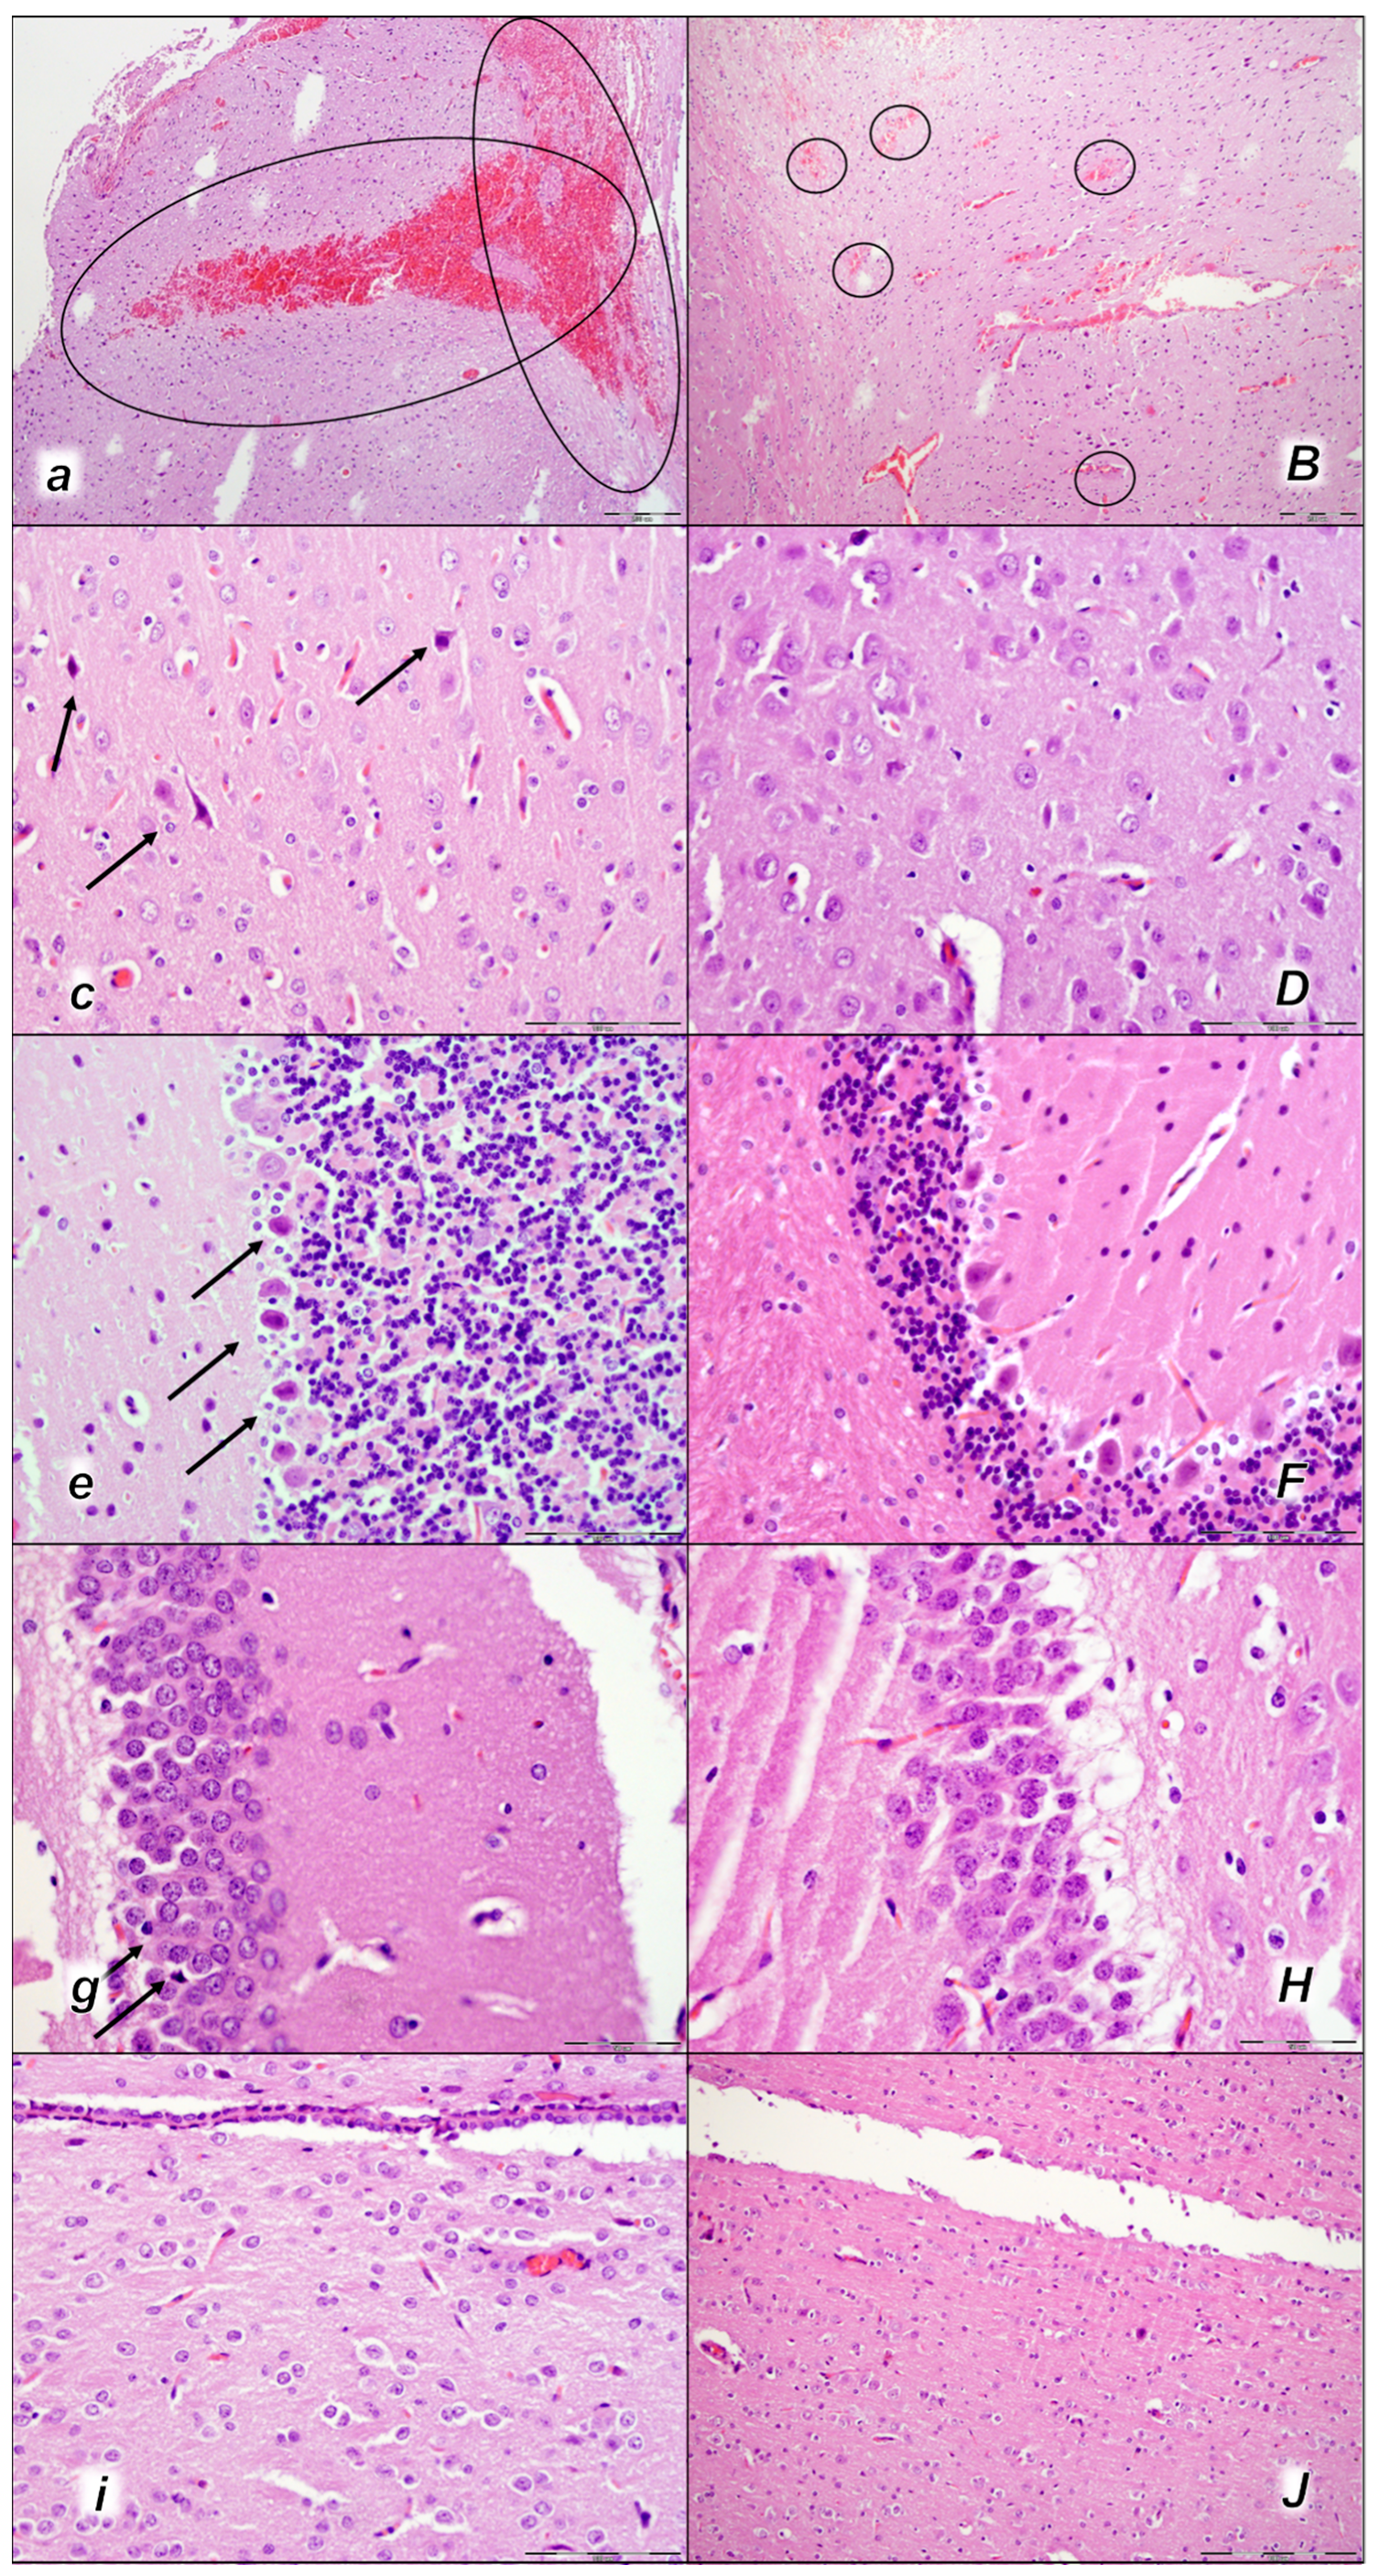

Figure 9.

Kidney, microscopy presentation (a–F). After laurate application into the inferior caval vein control rats (small italic letters), moderate vascular congestion was shown in renal parenchyma, interstitial edema at 15 min (a), and moderate vascular congestion, and interstitial edema, and intratubular hyaline casts (black arrows) at 30 min (c,e) and at 60 min (g,i). No changes in BPC 157-treated rats (capital italic letters) were observed at 15 min (B), 30 min (D,F), and 60 min (H,J) after laurate application into the inferior caval vein. (HE staining; magnification 200×; scale bar 200 μm (a,B,c,D,g,H); magnification 600×; scale bar 50 μm (e,F,i,J)).